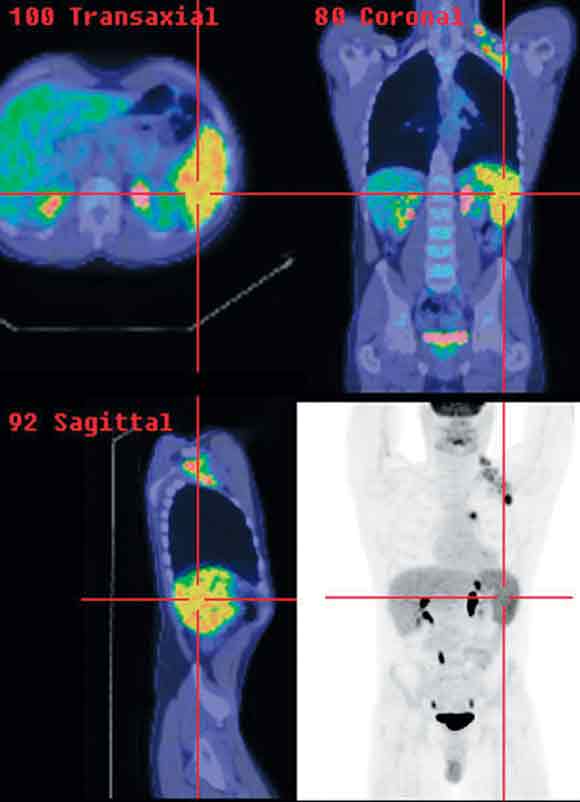

3 Positron emission tomography/computed tomography images of Hodgkin’s disease staging

Clinical stage I left axillary disease was upstaged to stage IIIs because of mediastinal nodal and splenic involvement detected on PET/CT.